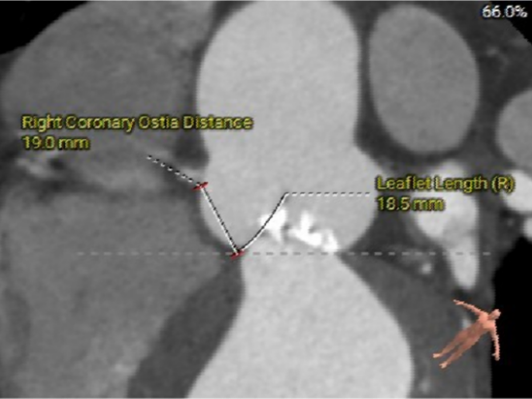

· 冠脉开口高度可,右冠纤细,冠脉未见明显钙化;

RCA&LEAFLET

· 冠脉开口高度可,右冠纤细,冠脉未见明显钙化,结合瓦氏窦及STJ尺寸预估,冠脉风险适中,建议术中密切关注左冠灌注情况。